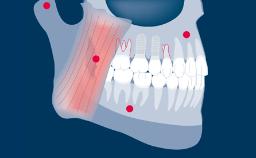

German Gallucci